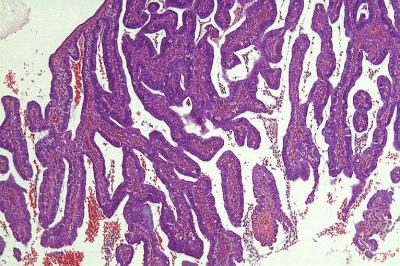

Figure 1: Exophytic tumour composed of villous and papillary architecture (H&E, 10x  magnification)